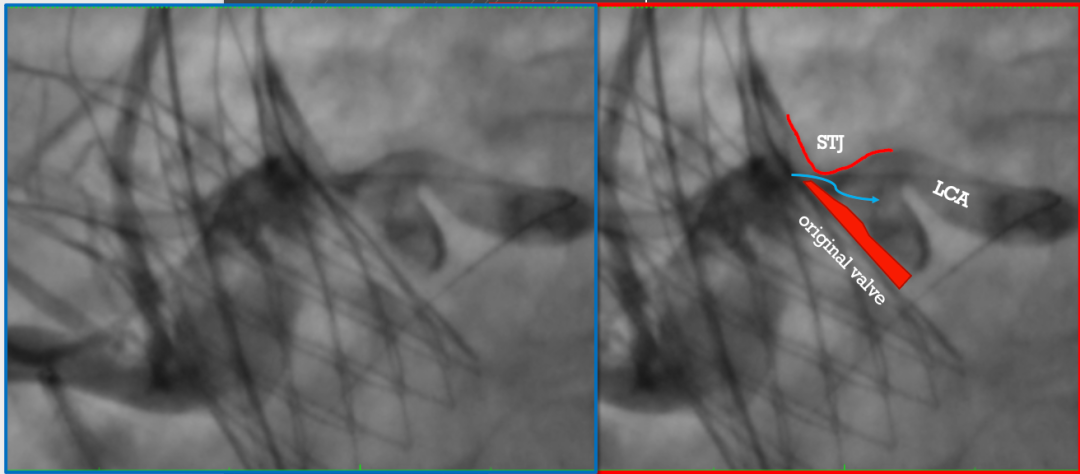

左冠口疑似遮挡

IVUS检查冠脉开口,

进一步精准评估冠脉开口遮挡情况

IVUS检查提示因原瓣叶遮挡,左冠开口受阻,最窄处残余缝隙0.66-0.82mm。